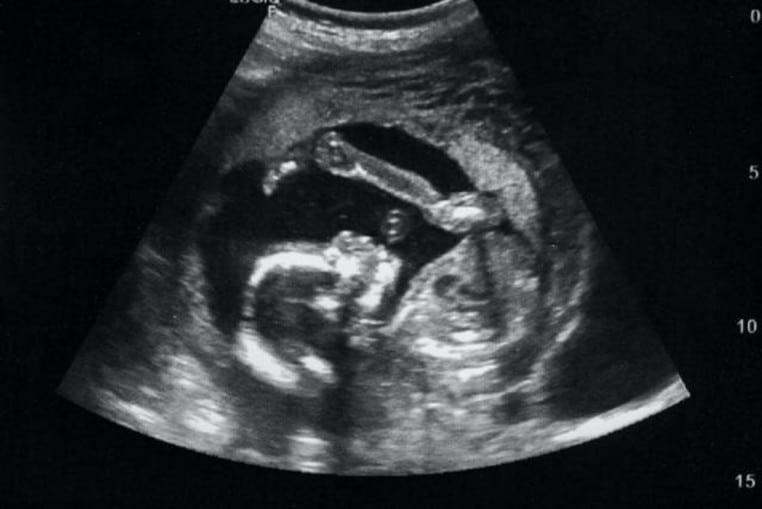

D’après le constat des médecins, le fœtus a connu une croissance tout à fait normale dans le ventre de cette femme. Mais puisque Zahara Boutaleb n’a pas accouché, le bébé est mort d’asphyxie ! Plus tard, son corps a développé une coque calcaire autour du fœtus pour le protéger. En même temps, elle a constaté qu’elle n’a plus eu de problèmes de santé !

On ne sait pas si cette femme a ressenti une perte des eaux ou une quelconque douleur au neuvième mois. Mais d’après les médecins, une des explications les plus logiques se trouve dans la grossesse extra-utérine. Pour faire simple, le fœtus ne s’est pas développé dans l’utérus comme tous les autres. Il a préféré se nicher dans la cavité abdominale. De ce fait, il n’avait presque aucun espoir de survivre !

Au CHU Rabat, le professeur Ouazzani Taibi se charge du cas de Zahara Boutaleb. En regardant sa patiente, le médecin sait que cette femme court un grave danger s’il n’intervient pas ! Tout de suite, lui et son équipe procèdent à une série d’analyses. C’est là qu’ils découvrent la cause de son mal : un bébé de 3,7 kilos et de 42 cm.

On parle de bébé, mais s’il a survécu, il serait dans la soixantaine aujourd’hui ! La femme a dû subir une intervention chirurgicale afin de retirer le fœtus. La coque calcaire autour de lui l’a fossilisé. En même temps, le corps de sa mère s’est adapté à son existence !

D’après les médecins, la forme du bébé que cette femme a porté durant 46 ans s’appelle « lithopédion ». Il s’agit d’un terme médical qui désigne un « enfant de pierre » (litho veut dire pierre et pedion veut dire enfant en grec). Mais pour le grand public, il s’agit simplement d’un fœtus pétrifié !